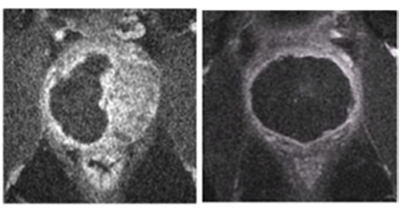

A large clinical trial across 47 European hospitals has shown laser photodynamic therapy (PDT) to be an effective treatment for early-stage prostate cancer, with no side effects.

Surgeons have just published the results of their randomized controlled study on more than 400 men in the journal Lancet Oncology. They found that, of the 206 patients to receive PDT, 101 (49 per cent) had a negative biopsy result when tested two years after the treatment, while in 58 (28 per cent) the disease had progressed.

At the same time, of the 207 men in the “active surveillance” group – who did not receive PDT – only 28 (14 per cent) showed a negative biopsy at the two-year follow-up, while 120 (58 per cent) tested positive for disease progression.

When injected into the bloodstream, that non-toxic photosensitizer stays in the patient’s blood stream for around four hours. During that time, illumination around the diseased tissues with a 735 nm laser activates the circulating drug locally, generating highly reactive oxygen and nitric oxide radicals that destroy the tumor and its blood supply - but without damaging nearby structures.